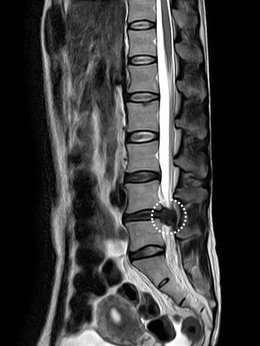

- MRI : 디스크의 위치와 상태를 정확하게 보여줍니다.